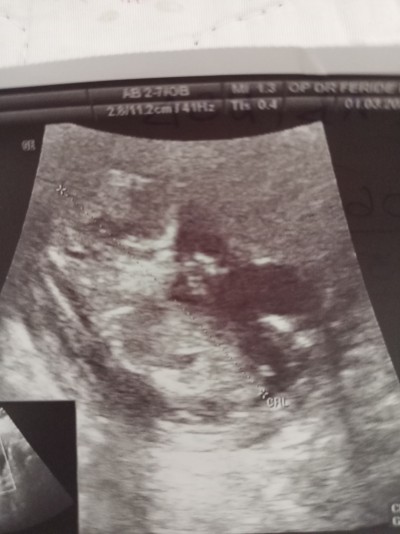

Bebeğim 12 haftalık biraz büyük mu ultrasonda mi öyle görünüyor

image

Bu bal kız bebek herhalde

Yazarım zaten kıza benziyor ama kesin değil hazırlık yapma dedi